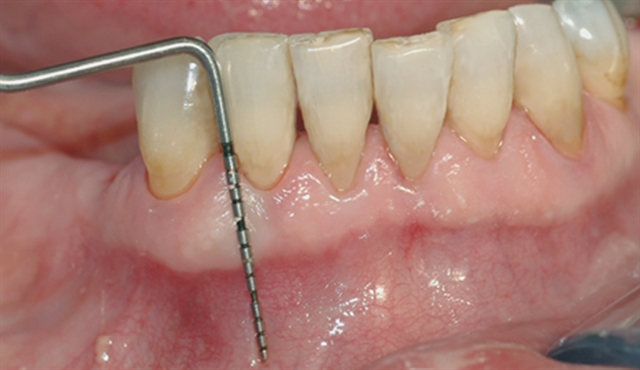

Bildet viser tilsynelatende normale tannkjøttsforhold ved tenner i underkjeven.

• perio stor 2

perio stor 2

En undersøkelse med lommeregistrering avdekker likevel et omfattende bentap ved den ene tannen.